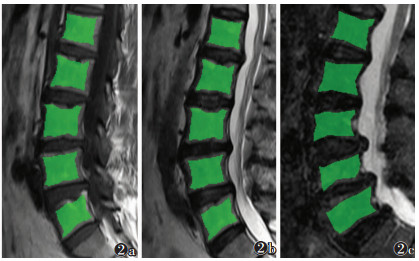

1.3 图像分析与纹理特征筛选将图像以DICOM格式从PACS导出至MaZda 4.6软件(http://www.eletel.p.lodz.pl/mazda/)。由2位具有5年以上影像诊断经验的医师协商后沿椎体边缘共同绘制ROI,ROI为累及病变的所有椎体,选择矢状位T1WI、T2WI和T2-STIR序列的正中层面图像,避开皮质和椎基静脉丛且不包含腰椎附件(图 1,2)。提取灰度级直方图、绝对梯度、灰度游程矩阵、灰度共生矩阵、自回归模型和小波变换6类纹理特征。然后通过软件提供的费希尔算法(Fisher coefficient,Fisher)、分类错误率+平均相关系数算法(classification error probability and average correlation coefficients,POE+ ACC)、交互信息算法(mutual information coefficient,MI)3种方法对3个序列进行降维筛选,每种方法筛选出10个最优纹理特征参数。

| 注:患者,男,67岁。图 2a为勾画矢状位T1WI序列的ROI;图 2b为勾画矢状位T2WI序列的ROI;图 2c为勾画矢状位T2-STIR序列的ROI 图 2 腰椎退行性病变的ROI绘制 |